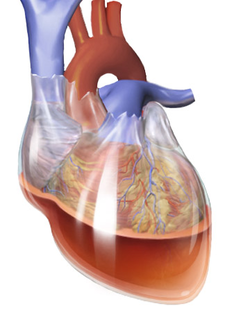

TAG: sesak napas

sesak napas

"Sesak Napas"